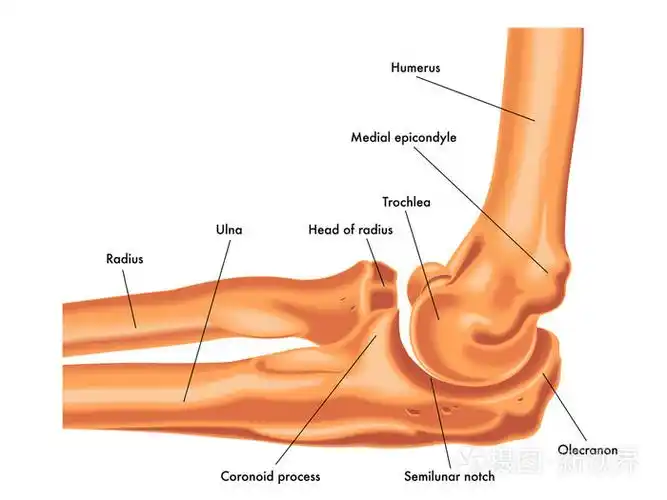

肘关节

2,软组织结构:肘关节周围的肌肉,韧带等和关节囊,如肱二头肌,肱肌和肱